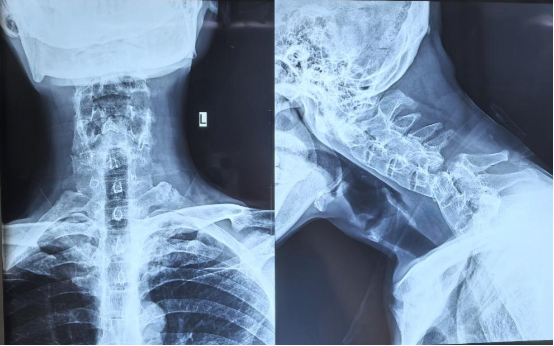

患者是一位中年男性,罹患强直性脊柱炎多年,整个脊柱融合僵直,如同一根“脆弱的竹竿”。一次意外不慎跌倒,颈椎多处骨折并严重脱位,错位的椎体将最脆弱的脊髓神经挤压到极限,生命悬于一线。“就像一根即将被扯断的电线。”主刀医生闫铭副主任医师形容到。

对普通人而言,颈椎骨折属于高风险损伤,手术难度不言而喻。而该患者脊柱僵硬,还伴有严重骨质疏松,所需植入螺钉时,如同在“酥饼上雕刻”,稍有不慎就会失败。更棘手的是,长期病变让正常的解剖结构完全混乱,医生手术视野中失去了所有熟悉“路标”。每一次操作都如同在雷区中穿行,随时可能损伤血管和神经,造成灾难性后果。

常规手术方案无法满足,但不及时手术,患者将面临生命危险。“患者入院时已经出现上肢麻木、无力等症状,这意味着神经损伤正在进行中,”团队医生回忆。